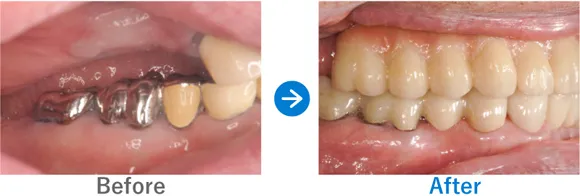

Case2

上下義歯の状態からインプラント治療後に自信を取り戻された方

上下義歯(入れ歯)ほとんど歯が残っていない、残存歯は上顎1本下顎5本のみ。

上顎骨がやせていて普通にはインプラントが出来ない状態。

上顎ザイゴマインプラントでALLON4、下顎ALLON4

10,703,000円(上顎7,128,000円、下顎3,575,000円/内訳:上顎オールオン4(ノーベルザイゴマインプラント4本)、下顎オールオン4(ストローマンインプラント4本)、3Dモデルガイド*、仮歯、セデーション、ボツリヌストキシン注射、3D模型、保証10年)

*単体のインプラントのガイドとは異なる、オールオン4専用のガイド

※当時の価格で現在とは異なる場合があります。

来院の背景

60代前半から現在の義歯を使っている。初めはピッタリだったが、だんだんと義歯がゆるくなり、鈎歯(こうし)が折れた。歯がダメになったら、インプラントを検討しようと思っていた。ご主人のご友人がインプラントをしたため興味を持ったが、金額もかかるため、家族には相談せずに来院された。

治療結果

上顎ザイゴマインプラント4本。下顎ALLON4で行った。治療完了後、現在もメンテナンスで来院中で経過良好。口元が綺麗になり、お化粧をするなど美意識が高まり、おしゃれに気をつかうようになったとのこと。「笑顔が増えて、よく外出するようになりました。自信がつきました。」